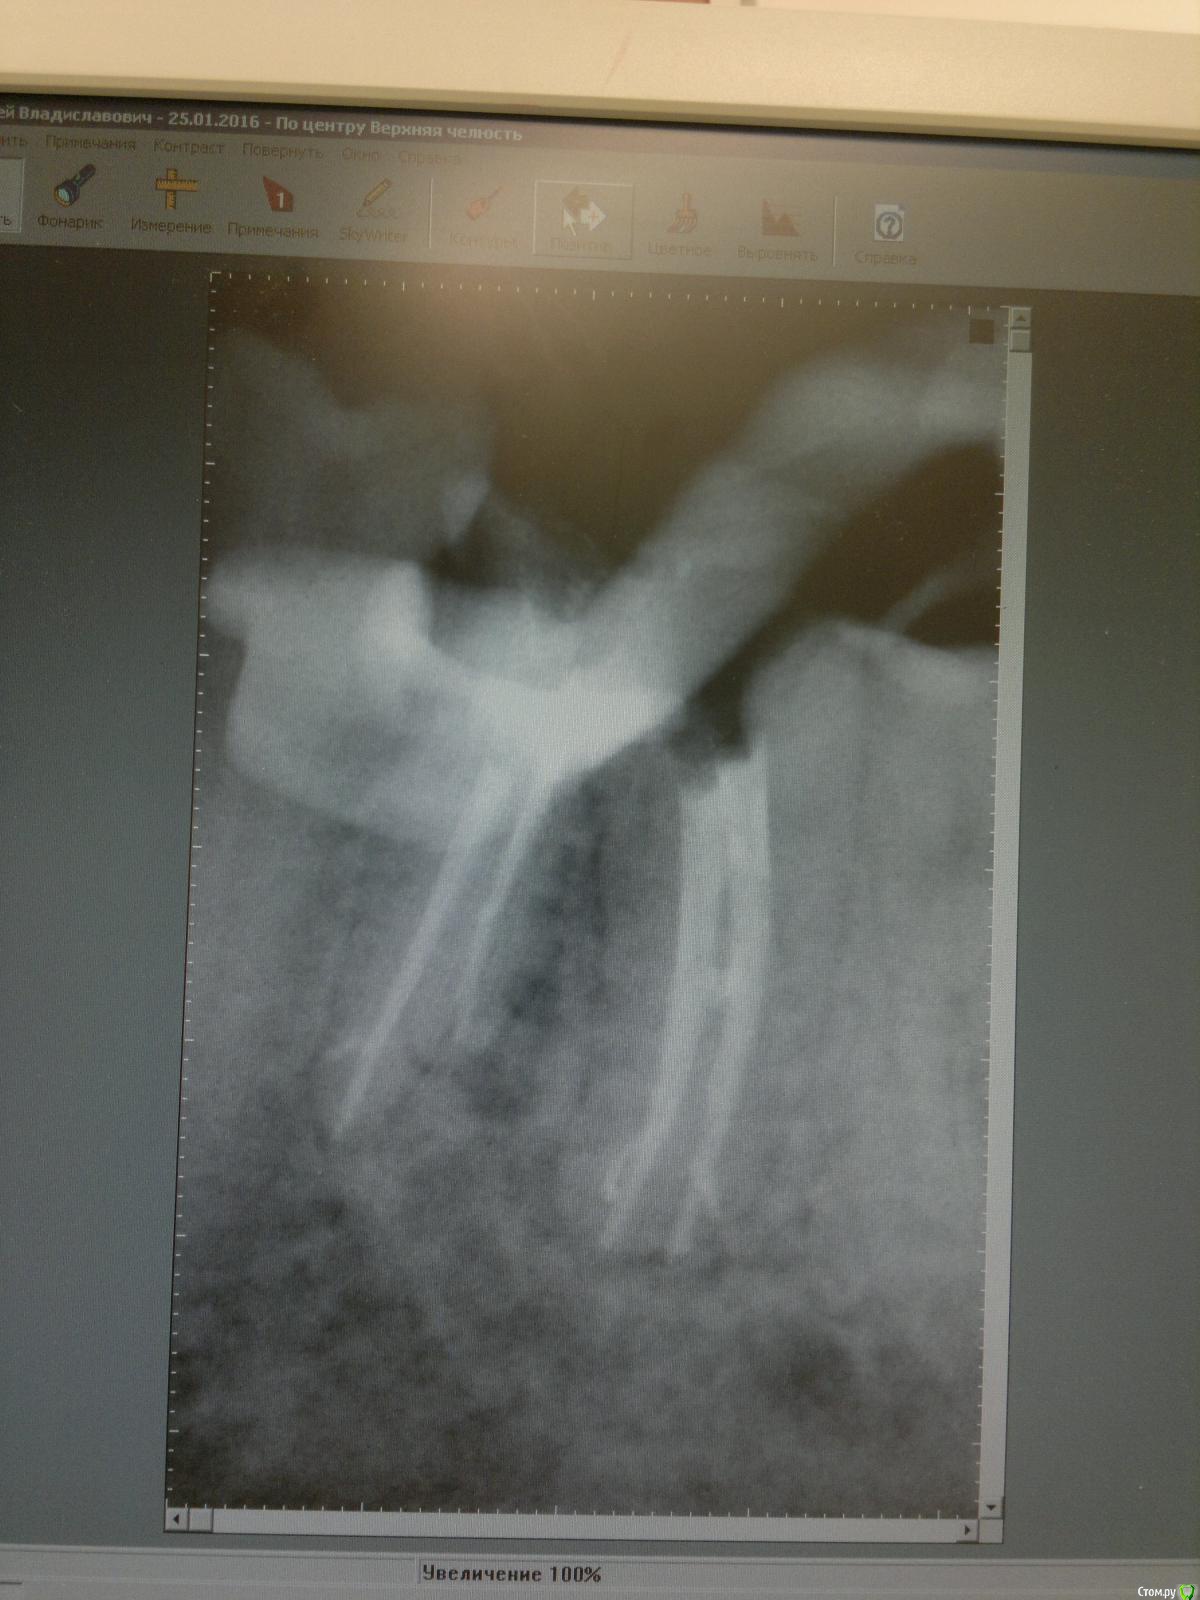

Ico Опубликовано 2 июня, 2016 Поделиться Опубликовано 2 июня, 2016 Штифты чаще меньше, чем заявленный размер, поэтому не калибрую добавочные Даже №30 не помню уже когда и брал. Все чаще 25ым обхожусь. .Примерно так же.Но бывают и исключения,и они хорошо видны на снимке,как будто не отжал на определенном участке канала,а это как раз мог быть тот заветный добавочный штифт который ел после 18)))) 1 Ссылка на комментарий